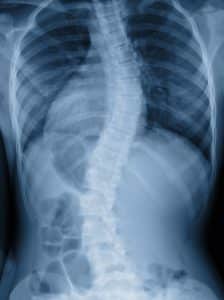

Can Adults Develop Scoliosis?

Dr. Branko Skovrlj, the founder of NU-Spine: The Minimally Invasive Spine Surgery Institute, is world-renowned for his contributions to treating spinal deformities. He and his expert medical team perform cutting-edge procedures to help patients relieve symptoms of scoliosis, including adults, at locations in Paramus, Woodbridge, Toms River, Jersey City, and Holmdel, NJ. Here, we discuss the signs and symptoms most commonly seen in adult scoliosis patients, as well as the importance of seeing a spine specialist.